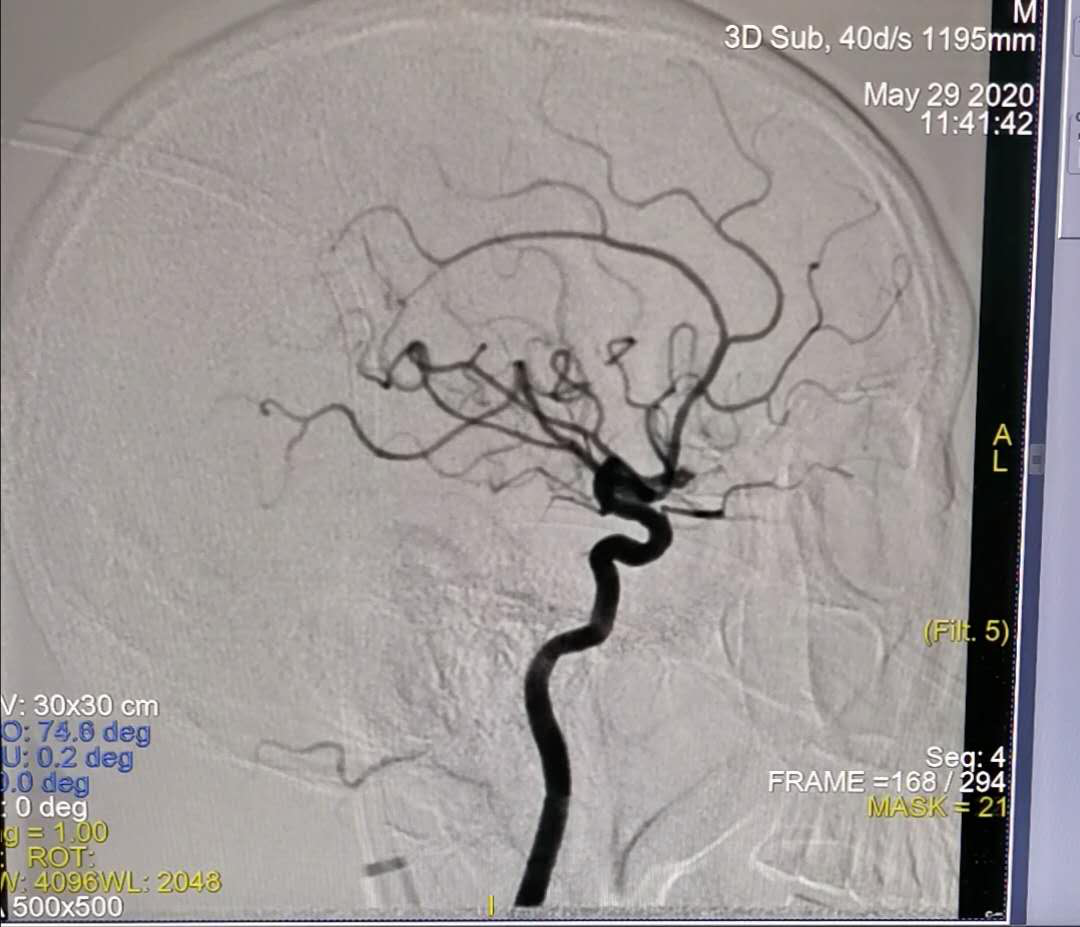

图2:术后侧位造影

一直以来,我院在诊疗自发性蛛网膜下腔出血方面,经验少,手段有限,患者不得不转外院治疗,以至于给患者造成巨大经济负担。自2018年神经外科二病区顺利开展了颅内动脉瘤开颅夹闭手术后,为诊治“自发性蛛网膜下腔出血伴颅内动脉瘤破裂”行开颅夹闭积累了一定经验。2019年底,我院安装了GE大型数字剪影血管造影机,主任康宏达带领科室医师积极开展新业务,新技术,目前可通过神经介入动脉瘤栓塞治疗颅内动脉瘤,为自发性蛛网膜下腔出血患者提供了另一种治疗选择。